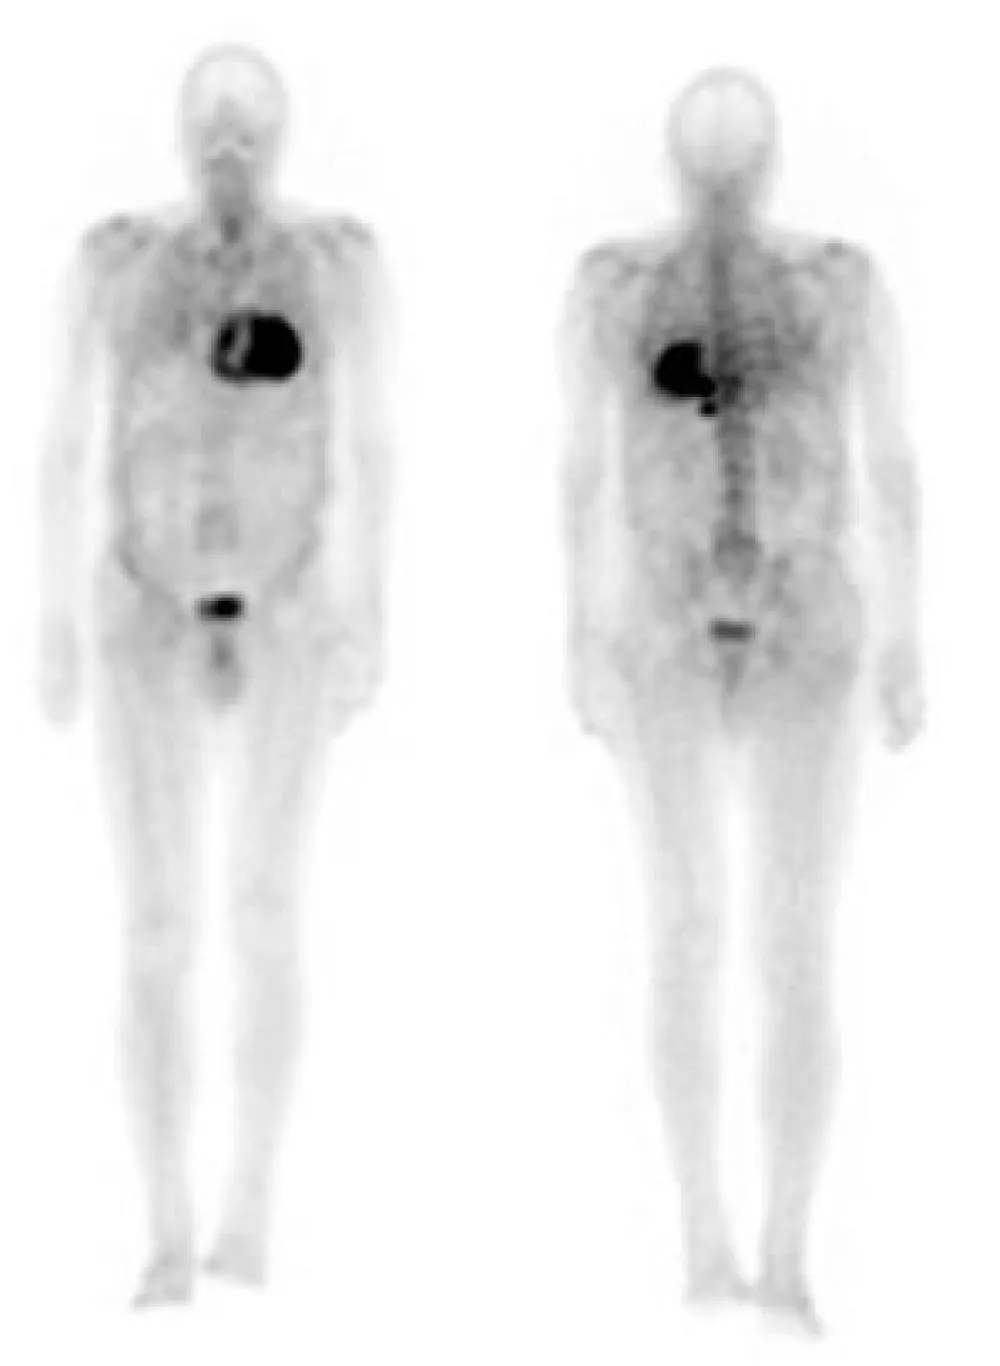

In order to identify the origin of amyloidosis, a Tc99m-DPD scan was requested, after obtaining written patient informed consent, a planar whole-body scintigraphy was performed 2 hours after intravenous injection of 740 MBq, that showed intense biventricular myocardial tracer uptake grade 3 (greater than the bone uptake), compatible with cardiac TTR amyloidosis, (Figures 1,2). Finally, a Genetic Testing resulted negative for TTR gene Mutation, which is consistent with the diagnosis of cardiac amyloidosis ATTRwt.

Figure 1: Anterior and posterior views whole body 99mTc-DPD scan. Marked myocardial uptake, suggesting an amyloid infiltration.

Bone tracer scintigraphy, using 99mTc-DPD, 99mTC-HMDP, and 99mTc-PYP, has been employed as a diagnostic test for ATTR. It is proven to be more than 99% sensitive for grades 1, 2, and 3 (the grading visual score, considers the myocardial tracer uptake compared with the bone uptake: grades 1 less than the bone uptake, grade 2 equal to the bone uptake and grade 3 greater than the bone uptake), and 97% specific for ATTR amyloid in the presence of grade 2 or 3 cardiac uptake [11]. It should be carried out under clinical suspicion for ATTR in the absence of monoclonal protein in the urine with a positive predictive value of 100% [11], as this case exhibits. Although the precise mechanism of DPD uptake in myocardium with amyloid deposits is not completely understood, it is likely due to the high calcium content in transthyretin amyloid fibrils [11].